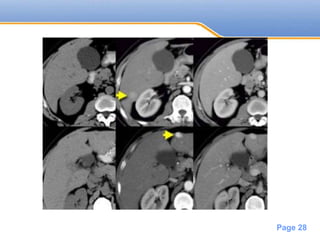

• #28 Small HCC seen only in arterial phase in a patient with cirrhosis

• #29 NECT, arterial and portal venous phase in a patient with Hepatitis C with two lesions in the liver (arrows)

• #30 CT scan of the abdomen with quadrephasic liver protocol was performed which confirmed the presence of a hyper-vascular lesion in segment 3, demonstrating washout on portovenous phase.